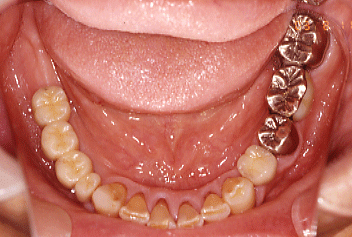

2006.11.29 |45と左下6にインプラント